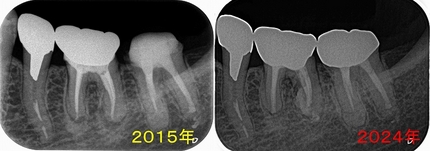

ん~、水酸化カルシュウムが歯の外に押し出しているように見えます。

抜いた歯には根尖病変内に水酸化カルシュウム

そもそも論なんですが、根尖病変の原因は細菌感染でその結果として骨の吸収が起こります。

つまり溶けた骨にアプローチしても殆ど意味ありません。。。